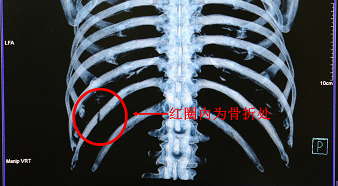

背部出现的红肿和疼痛起初并没有引起赖钊的重视,期间他仍旧正常工作,直到7月26日他在咳嗽时感到疼痛加剧、活动受限,这时一种不祥的预感促使着他来到医院检查。检查报告单证实了赖钊的判断——左侧第11肋骨折。胸心大血管外科医生劝他住院治疗被他婉言谢绝,穿戴上固定带后,赖钊离开了胸心大血管外科。